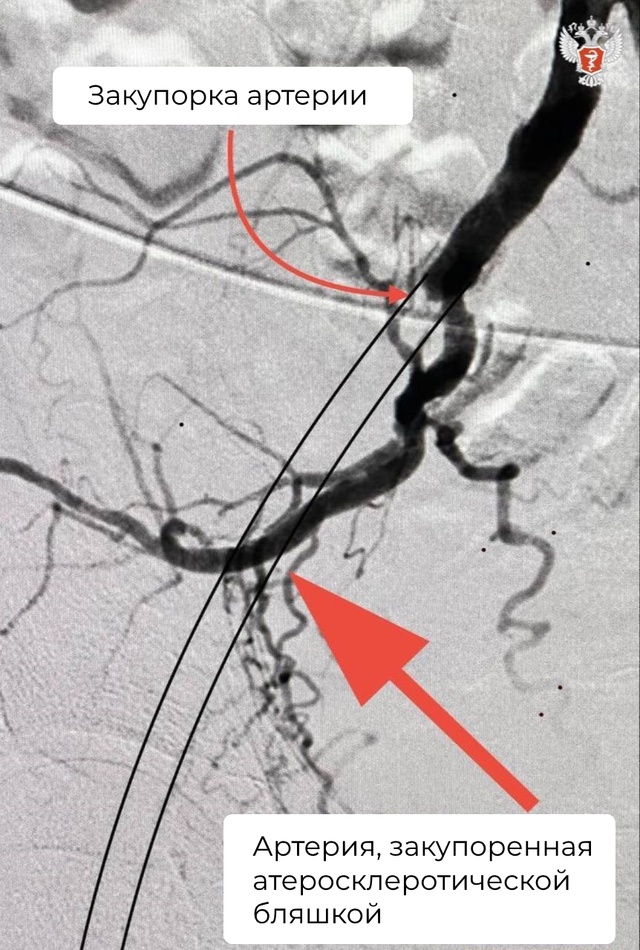

➡ По результатам обследования врачи диагностировали закупорку общей подвздошной артерии.

Пациента госпитализировали для проведения операции. В ходе вмешательства врачи восстановили проходимость подвздошной артерии и установили стент для расширения просвета.